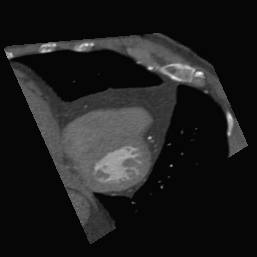

4.2.1 Internal Testing - Comparison with Existing Methods

We select two typical comparison methods to validate the effectiveness of our framework AVP-AP in the 20 target CT volumes of Dataset 1, which employs the atlas prompts with the best configuration in Section 4.3. Table 1 presents the comparison results among the optimization-based method Opt-SVR [15], the learning-based method Lea-AVP [19], and our proposed framework AVP-AP. We can observe that our framework AVP-AP outperforms Opt-SVR by a large margin, and achieves a 4% improvement in SSIM of the 2C view compared to Lea-AVP. This reveals that iterative optimization methods struggle to accurately locate arbitrary 2D slices within a large 3D search space because it usually depends on a well-initialized position. In contrast, the learning-based methods can more precisely locate certain standard slices by using prior anatomical knowledge. However, the learning-based methods for automatic view planning, such as Lea-AVP, are unsuitable for locating arbitrary slices. As a result, the metrics of the Y and RV1 views in Table 1 cannot be calculated, limiting their applicability. Fig. 4 presents the visualization of the results from the other methods and our proposed framework AVP-AP. It can be seen that our results are better than Lea-AVP on 2C and comparable on 4C, while Lea-AVP cannot position the arbitrary Y and RV1 slices. Hence, our framework can accurately position arbitrary 2D slices in arbitrary target 3D CT volumes through our designed atlas prompts, in comparison to existing methods. At the same time, it can be noted that our atlas prompting provides a well-initialized coarse position in the target CT volumes, significantly reducing the search space.

(a) 2C

(b) 4C

(c) Y

(d) RV1

To verify the real-world clinical application ability of our framework AVP-AP, we compare our positioning results with those of four radiologists. As shown in Table 2, we can see that our proposed method accomplishes an average improvement of 6.8% in SSIM for arbitrary slice positioning compared to four radiologists. This proves that our approach achieves a better level of performance than clinical experts in view positioning from a large 3D CT volume space. As shown in Fig. 4, we can observe that the results of our AVP-AP in automatic view positioning are highly similar to the slices annotated by radiologists, especially on the 2C plane, where the images obtained by our proposed method are even closer to the query images, particularly regarding the structure of the left ventricle. This verifies the clinical applicability of our proposed framework AVP-AP in view positioning.